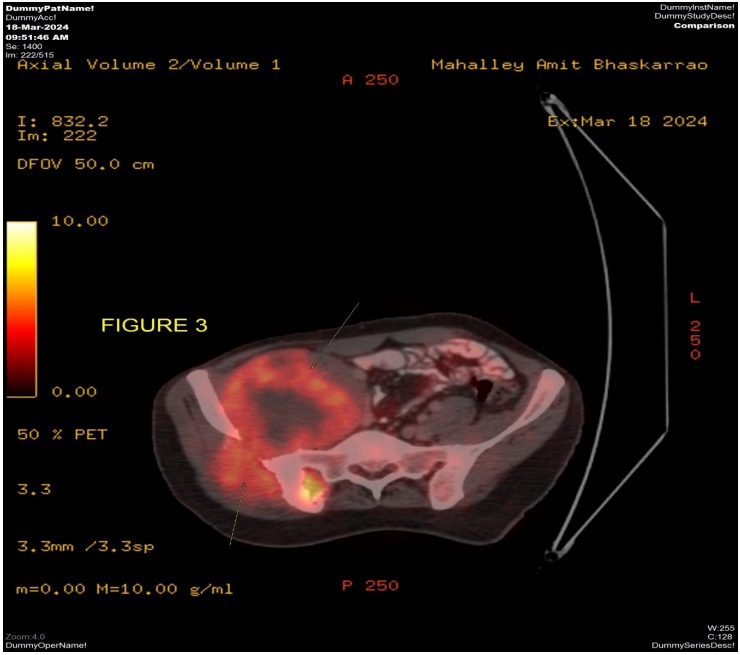

The patient underwent MRI pelvis (Fig 1 & 2) and PETCT (Fig 3 & 4) for initial evaluation (03/2024) at our institute which showed ill-defined large altered signal intensity heterogeneously enhancing mass in the right lumbar region with both intra as well as intrapelvic component by causing erosion of the right iliac bone involving the adjacent iliopsoas and gluteus muscles with central necrosis. On PET-CT scan the lesion showed significant FDG uptake with no other abnormality in the rest of the scan. Text the patient was planned for neoadjuvant chemotherapy and then for surgery. Patient took 2 cycles of neoadjuvant chemotherapy (Holoxan and Adriamycin), but after 2 cycles of chemotherapy response evaluation MRI was done (01/07/2024) (Fig 5) which showed increase in the size of lesion, so patient was planned for targeted therapy ie tyrosine kinase inhibitors, Pazopanib.

Figure 3: PETCT scan dated 03/2024 axial pelvic view shows ill-defined heterogeneous significantly FDG avid necrotic mass involving the right lumbar and pelvic region causing erosion of the adjacent right iliac bone and transverse process of S1 and S2 Vertebrae with both intra as well as extrapelvic component.

Figure 3